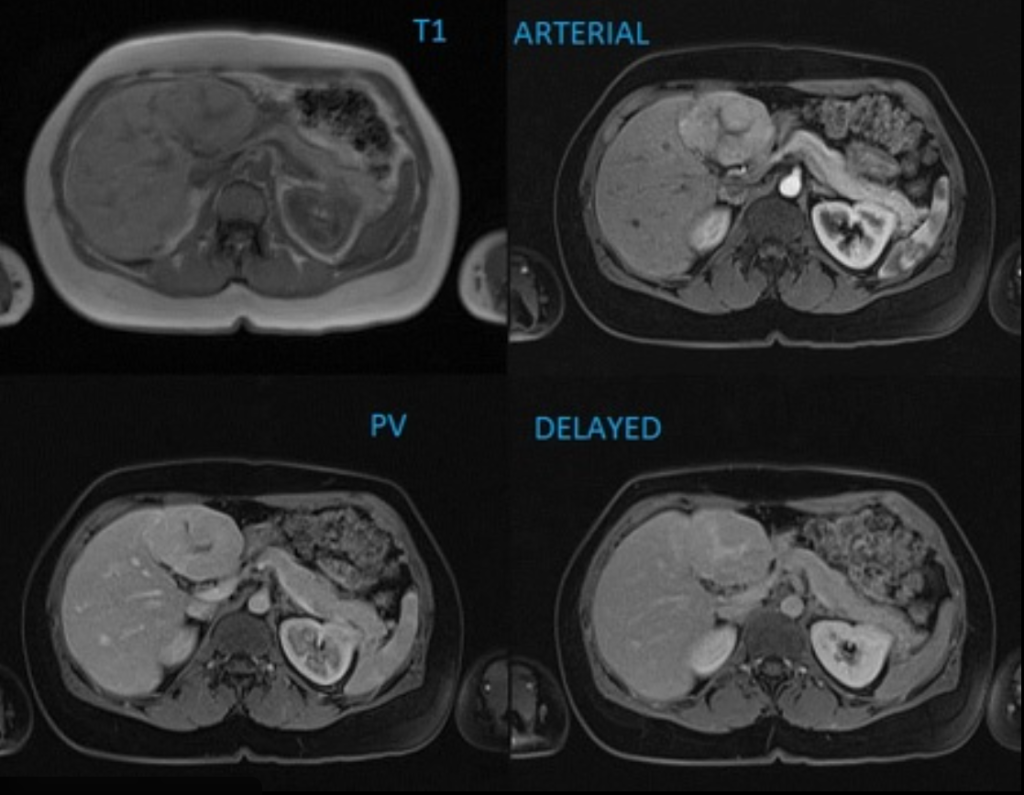

CASO 3

Donna di 32 anni, incidentaloma epatico di 4 cm. APR: Nessuna epatopatia, nessuna cirrosi. Assume contraccettivi orali.

Quale caratteristica permette di distinguere questa lesione da un adenoma epatico?

A) Enhancement arterioso precoce

B) Presenza di cicatrice centrale

C) Assenza di wash-out portale

D) Iperintensità in fase epatobiliare

E) Dimensioni > 3 cm

Risposta esatta: D

FNH:

Si tratta di iperplasia nodulare focale (FNH).

La chiave è la fase epatobiliare:

- La FNH contiene epatociti funzionanti → capta il mezzo di contrasto epatospecifico

- L’adenoma generalmente appare ipo-intenso in fase epatobiliare

La cicatrice centrale aiuta, ma non è sempre presente.

L’enhancement arterioso non è discriminante (anche l’adenoma è ipervascolare).